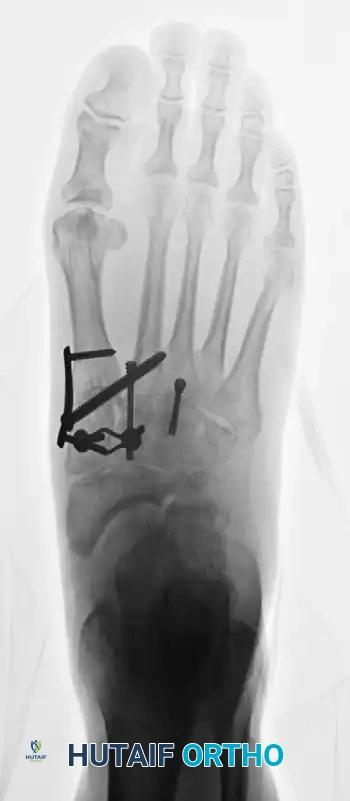

بمجرد تحضير المفاصل، يتم وضع القدم في وضعية مسطحة طبيعية ومستقرة، ويتم تثبيتها بشكل مؤقت باستخدام أسلاك كيرشنر الطبية.

يبدأ الجراح برد وتصحيح مفصل المشط الأول، والذي غالباً ما يكون منحرفاً، ثم يتم ضبط المفاصل الأخرى بناءً على هذا العمود الداخلي الذي أصبح مستقراً الآن. يتم إيلاء اهتمام خاص لضبط الزوايا في المستوى السهمي لتجنب حدوث آلام في مشط القدم مستقبلاً.

بعد التأكد من التصحيح المثالي وتطابق العظام باستخدام الأشعة، يتم التثبيت النهائي. تتوفر أشكال متعددة من التثبيت، وغالباً ما يُفضل استخدام براغي مجوفة بقطر 4.0 ملم بتقنية الشد لضمان انضغاط العظام معاً بقوة.

في بعض الأحيان، يتم استخدام شرائح معدنية ظهرية مصممة خصيصاً، أو شرائح داخلية لزيادة الاستقرار، وهو ما يتطلب تسليخاً دقيقاً ووضع الشريحة أسفل وتر الظنبوب الأمامي.

بالنسبة للبراغي التي تحتوي على رؤوس، يتم عمل تجويف صغير في العظم لدفن رأس البرغي، وذلك لتجنب كسر القشرة العظمية العلوية عند شد البرغي.